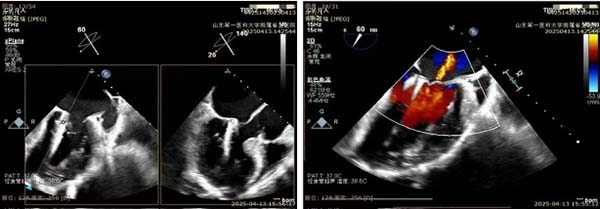

术前二尖瓣重度返流,

主动脉瓣中度返流